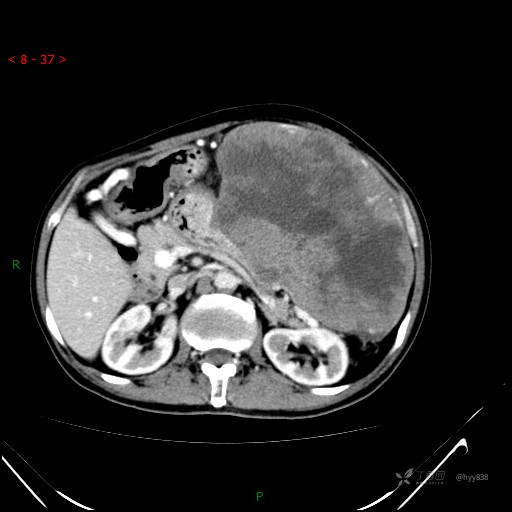

增强静脉期